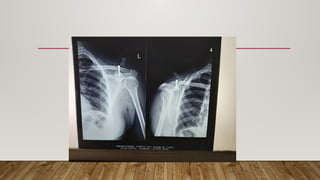

• 30 yrs/ F with history of fall from scotter

sustaining injury to left shoulder

• 64Y/M with AC joint injury Type 3